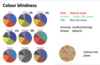

- Colour blindness

Colour blindness

Multiple forms depending on which cones affected and if total loss or problem with functioning.

Red-green colour blindness is most common and usually mild (anomaly)

Uusually tested with ishihara test plates